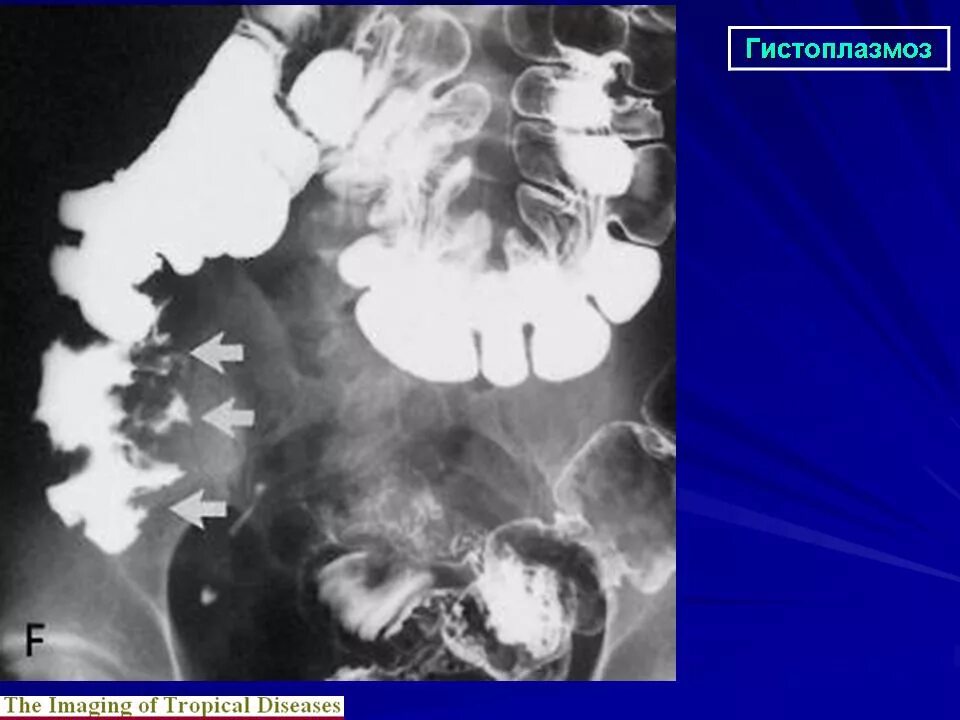

Гистоплазмоз это